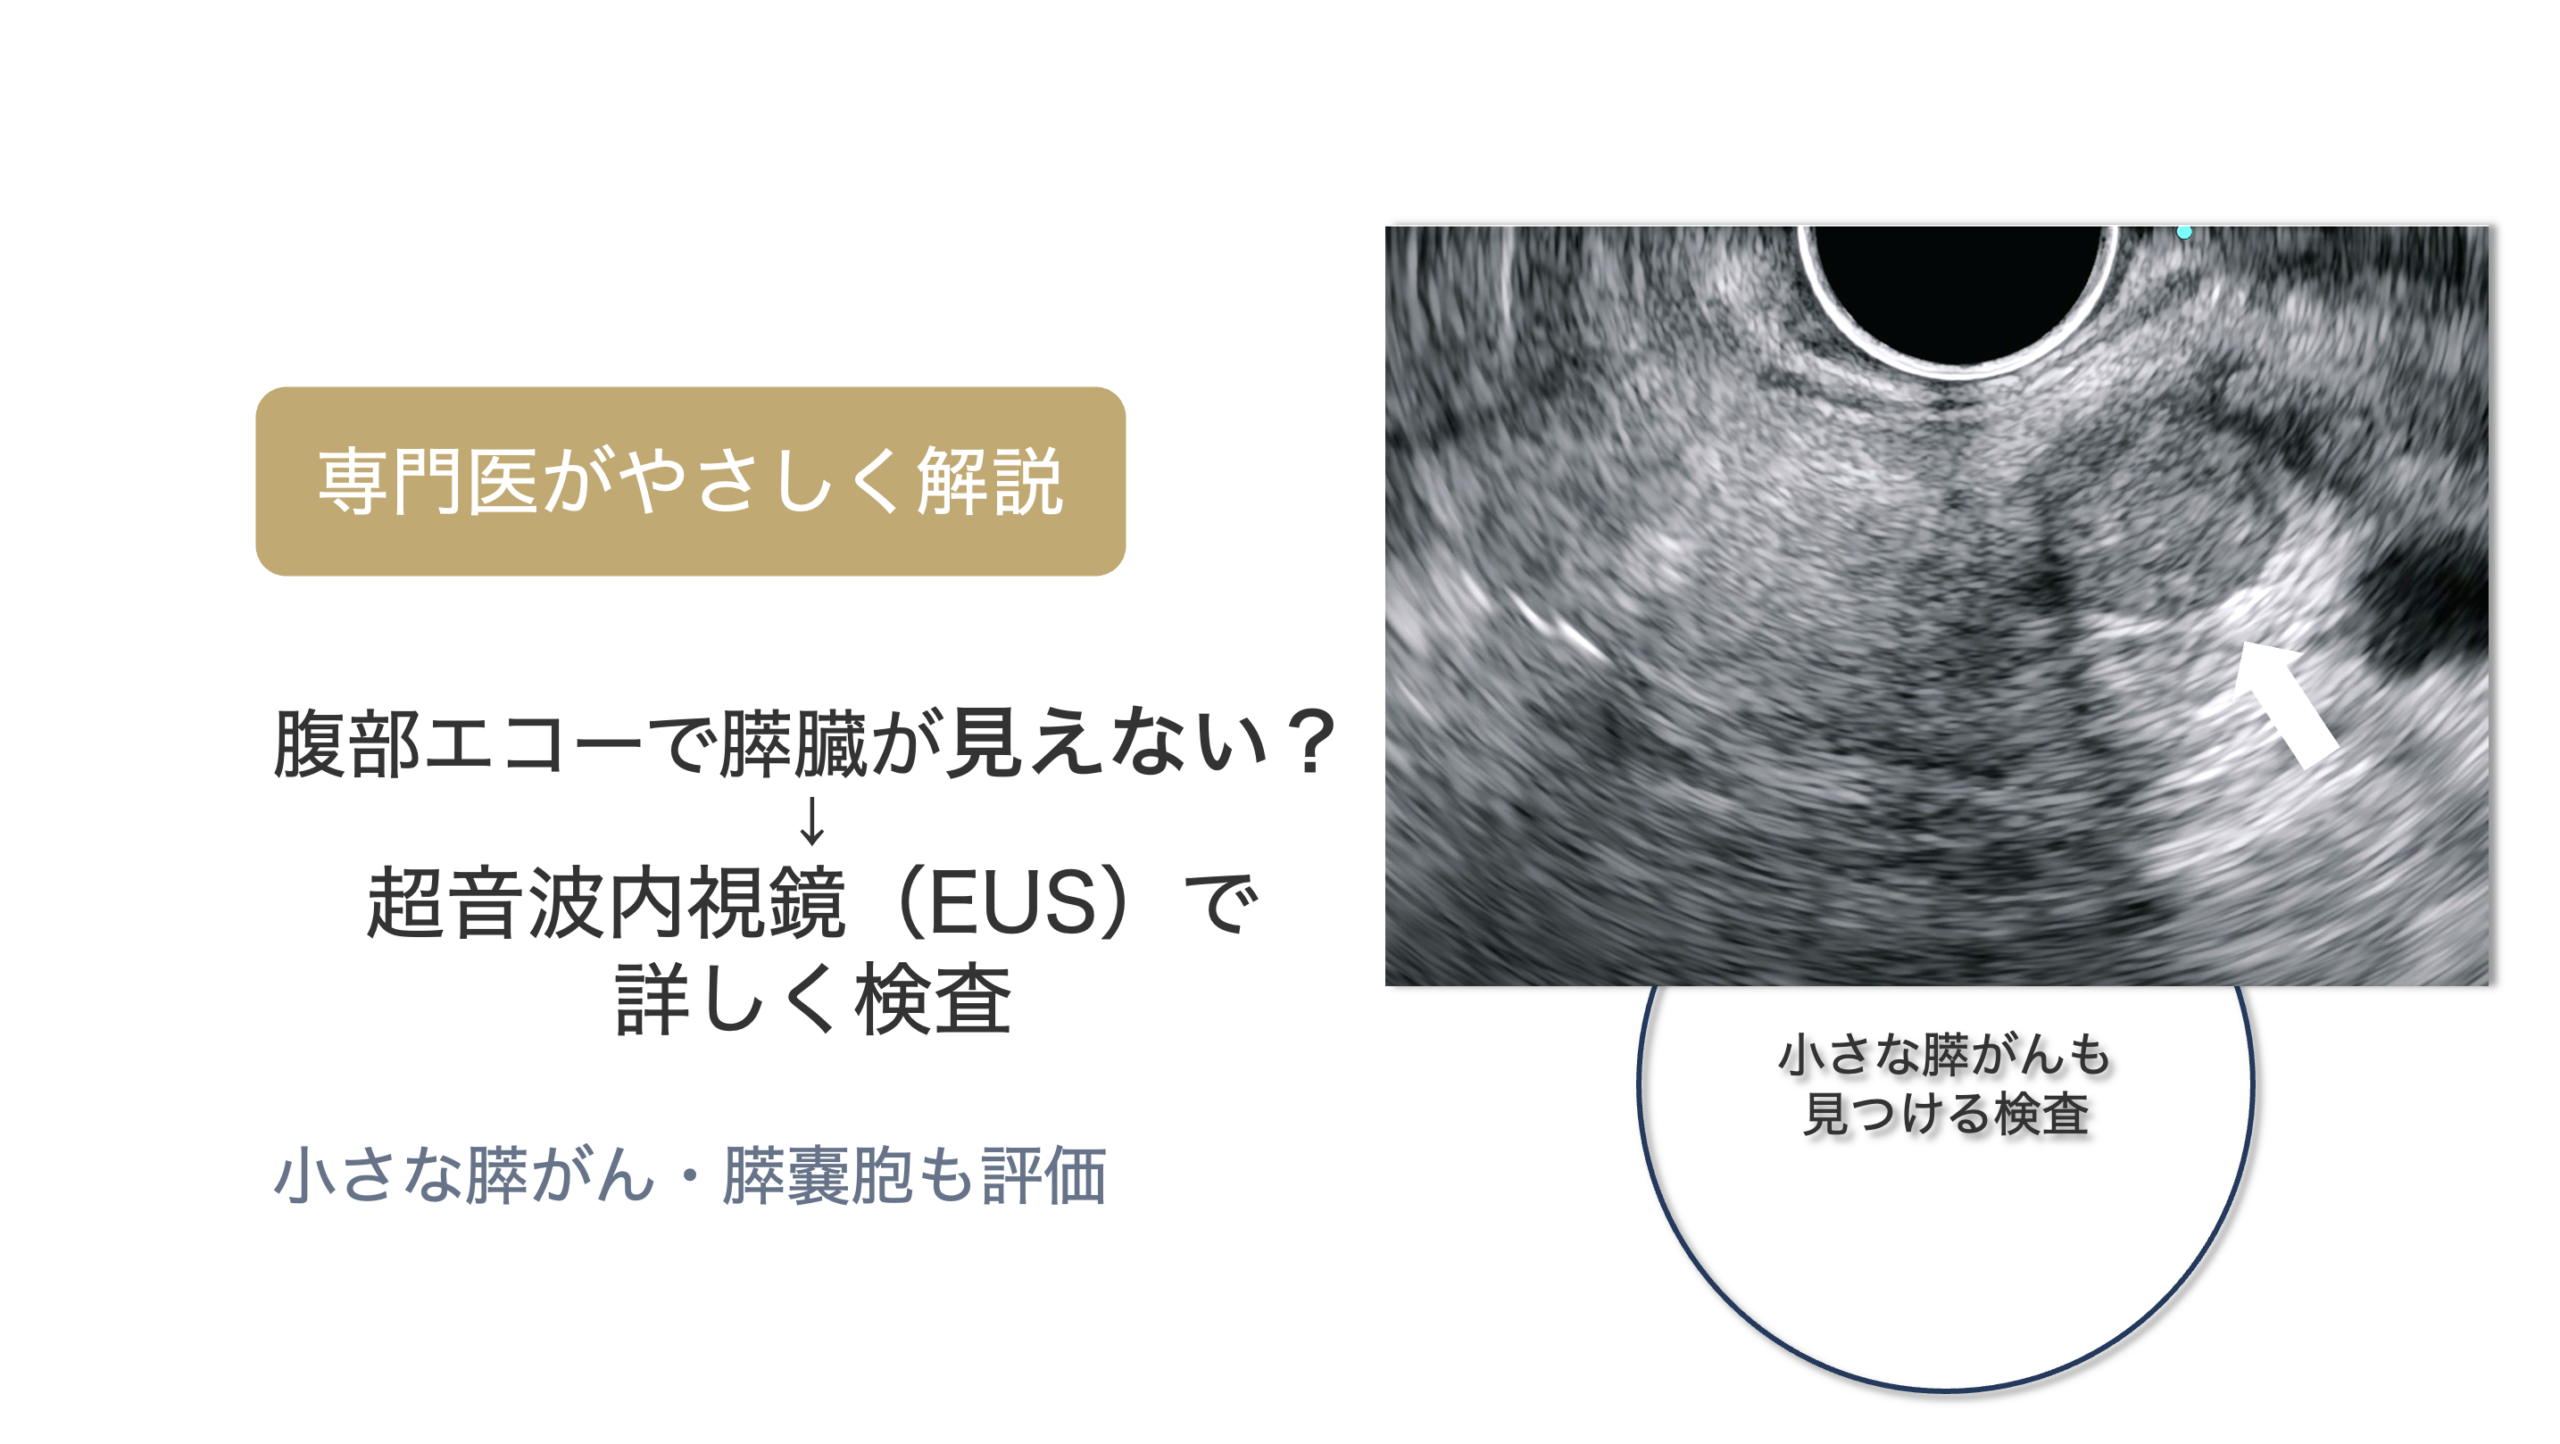

なぜ膵管拡張の評価に超音波内視鏡(EUS)が役立つのか

膵管拡張を指摘された場合、大切なのは「膵管がなぜ太くなっているのか」を確認することです。 腹部エコーやCT、MRI/MRCPで膵管の拡張が分かっても、 その原因となる小さな病変までははっきりしないことがあります。

超音波内視鏡(EUS)は、胃や十二指腸の中から膵臓の近くに超音波をあてて観察する検査です。 体の外から行う腹部エコーと比べて膵臓に近い位置から観察できるため、 膵管の狭くなっている部分や、CT・MRIでは分かりにくい小さな病変の評価に役立つことがあります。

EUSが検討されることがあるケース

✓ 膵管拡張の原因が腹部エコーやCTだけでははっきりしない場合

✓ 膵管が途中で細くなっている、または途切れて見える場合

✓ 膵嚢胞やIPMNを伴っている場合

✓ MRI/MRCPで追加評価が必要と判断された場合

✓ 糖尿病の急な悪化、体重減少、背中の痛みなどを伴う場合

ただし、膵管拡張がある方すべてにEUSが必要というわけではありません。 膵管の太さ、拡張の部位、膵嚢胞の有無、症状、年齢、全身状態などを総合的に見て、 MRI/MRCPで経過を見るか、EUSで詳しく確認するかを判断します。

他院の腹部エコーおよびCTで膵管拡張を指摘され、当院で超音波内視鏡(EUS)による精密検査を行いました。

他院の腹部エコーおよびCTで膵管拡張を指摘され、当院で超音波内視鏡(EUS)による精密検査を行いました。 膵臓に約8mmの腫瘍を認め、手術の結果、ステージ1の膵がんと診断されました。 通常の検査では見つかりにくい小さな病変が、EUSによって早期発見につながった症例です。

このように、通常の検査では見つかりにくい小さな膵がんも、EUSによって発見できることがあります。